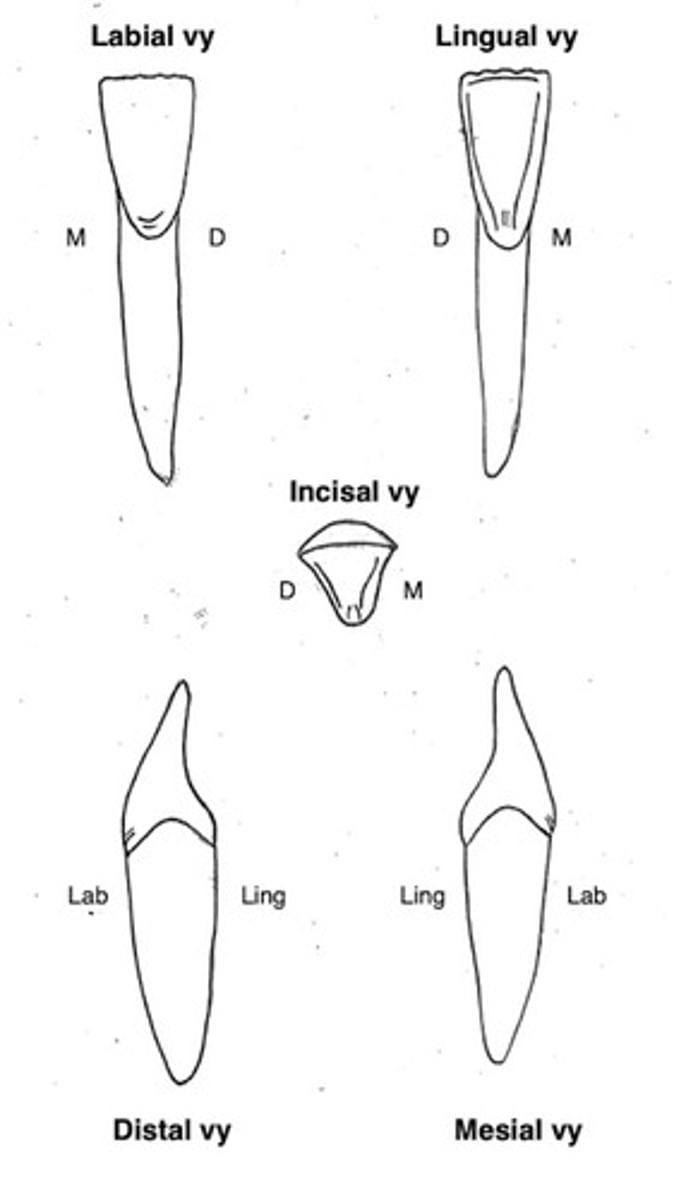

Centralerna i underkäken (31 och 41)

Kronans form?

Storlek?

Kronans form

- incisalt skär

- mejselformad

- saknar oftast vinkeltecken, böjningstecken och rottecken

- saknar oftast limbi och cingulum

Storlek

Bettets minsta och smalaste tand och rot

Underkäkens lateraler (32 och 42)

Kronans form?

Storlek?

Kronans form

- liknar underkäkscentralen fast kronan är större

- incisalt skär

- mejselformad

- har ofta men inte alltid vinkeltecken, böjningstecken och rottecken

- ofta men inte alltid limbi och cingulum

Storlek

- större krona än 31 och 41

- smal rot